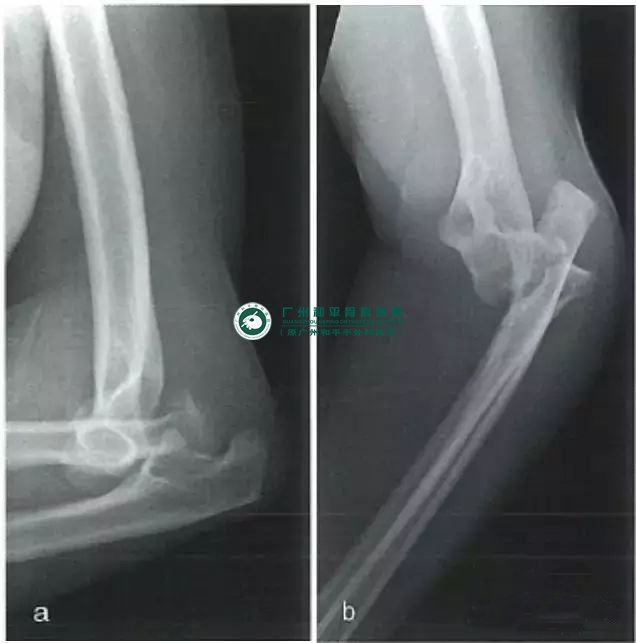

后方孟氏骨折脱位

此类损伤的发生机制与肘关节脱位类似,但脱位在近端尺骨粉碎骨折后出现,常合并累及冠状突或尺骨更远端的三角形或四边形骨折块。桡骨头常发生骨折并向后外侧脱位。外侧副韧带可能出现撕脱或撕裂,但内侧副韧带仍然完好。

如前所述,应用后方钢板重建尺骨近端可复位上尺桡关节。由后路用拉力螺钉直接固定冠状突骨折。有时通过牵引可使骨折自行复位。重建尺骨前方皮质的连续性是保证钢板起到张力带固定作用的关键。固定桡骨头骨折并修复外侧韧带结构,可为外侧柱提供足够的稳定性。

前方孟氏骨折脱位,侧位片提示尺骨近端粉碎骨折合并桡骨向前脱位